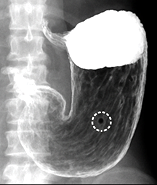

上部消化管造影検査は、食道・胃・十二指腸を調べる検査です。バリウムという液体を飲んでいただき放射線を使って撮影します。

バリウム検査は胃がんの早期発見のために有用な検査といわれ、日本では胃がん検診として多くの人に勧められています。

撮影直前に発泡剤という顆粒とバリウムを飲んでいただき食道・胃・十二指腸を撮影します。